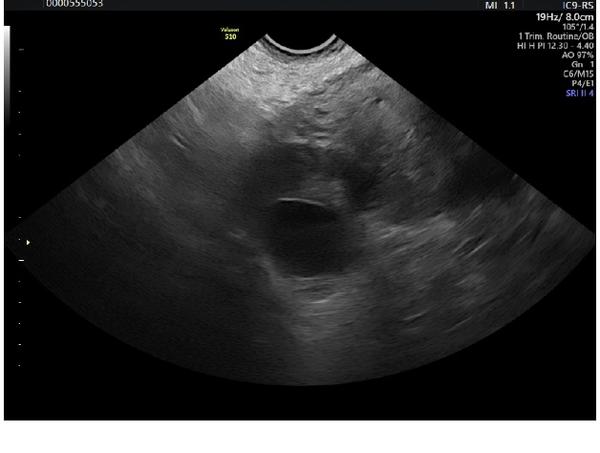

Mela jsem pridat vice informaci, pardon. Jsem po ivf, 2 embrya. Krevni test pozitivni, ale na ultrazvuku si nejsou jisti, zda neco vidi, krom 8cm cysty. Zkousim, zda nekdo nevidi neco vic. A ta cysta mi prijde desiva, take boli.

Jak dlouho po IVF? Já teď byla první den 7.tt a nebylo vidět ještě skoro nic, jen žloutkový váček

Myslím, že hcg je vysoké. 15.8. tak to už by zaznamenal i test - ale díky krvi není ani potřeba. Já otěhotněla podle všeho 6.8. a včera na utz nešlo ještě opravdu skoro nic vidět.